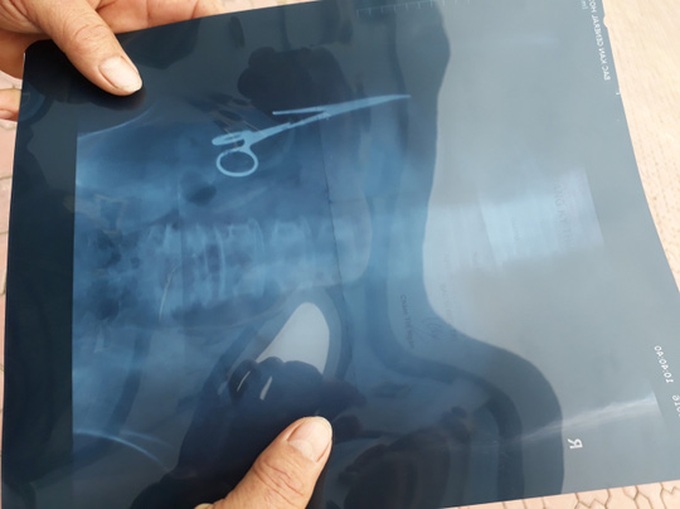

54-year-old Ma Van Nhat complained of a stomach ache and went to Thai Nguyen Iron and Steel Hospital. The ultrasound result on December 25 shows that there is a 15-centimetre-long pair of surgical scissors inside his abdomen. The ultrasound result at Bac Kan General Hospital also gave the same result.

Surgical scissors found inside Nhat's abdomen